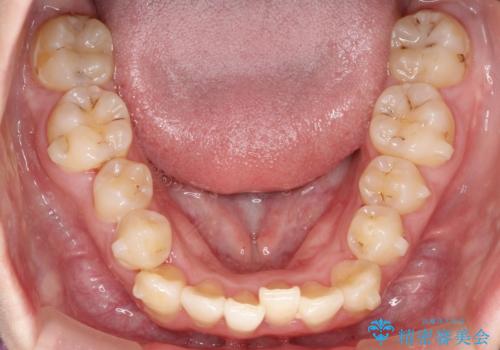

前歯が前後反対にかんでいる インビザラインによる矯正

- 前歯のがたつきを気にされて来院されました。

上顎の前から二番目の歯が内側に入り込んでおり、前後反対にかんでいる状態でした。

歯と歯の間にわずかに隙間を作り並べる計画としました。

しっかりとマウスピースを使用していただけたので、順調に治療を終えることができました。